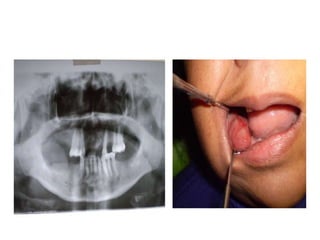

Se presenta como un nódulo firme,

suave, brillante o como una masa

que puede ser sésil o pediculada,

pudiendo variar de color, de un rojo

oscuro a púrpura o azul; su

superficie en ocasiones puede estar

ulcerada. El tamaño de estas

lesiones varía desde una pequeña

pápula a un agrandamiento masivo

pero generalmente son lesiones

menores de 2 cm de diámetro,

localizadas en la papila interdentaria,

en el reborde alveolar edéntulo o en

la encía marginal.

Radiología

En la mayoría de los casos la lesión se limita a la encía y no

hay afectación de hueso, sin embargo las células gigantes

podrían activarse como respuesta inflamatoria y actuar como

osteoclastos produciendo reabsorción del hueso alveolar. No

es usual pero existen casos reportados de reabsorción

superficial cervical de dientes asociados a esta lesión.

También se puede observar espaciamiento del ligamento

periodontal del diente involucrado. El estudio radiográfico es

importante en esta patología para determinar si es de origen

central con extensión a la superficie o es de origen gingival.